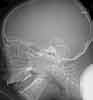

1. Eyelid swelling and discharge: The radiographsdemonstrate opacity of the ethmoid air cells on the left(A and B, black arrows) with increased opacity of theleft maxillary antrum, which is best seen on the frontalview (A, red arrow). The sphenoid and frontal sinusesare unremarkable. The increased density seen on thefilms results from the filling of the normally aeratedsinuses with opaque material (in this case, mucus).

Close inspection also reveals increased density ofthe left orbit (A, yellow arrow). This density is attributableto edema.